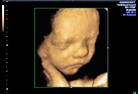

Als Facharzt für Frauenheilkunde und Geburtshilfe, freue ich mich, sie hier begüßen zu dürfen!

Infomieren Sie sich gerne über unser Leistungsangebot. Für Fragen stehen wir Ihnen gerne zur Verfügung.